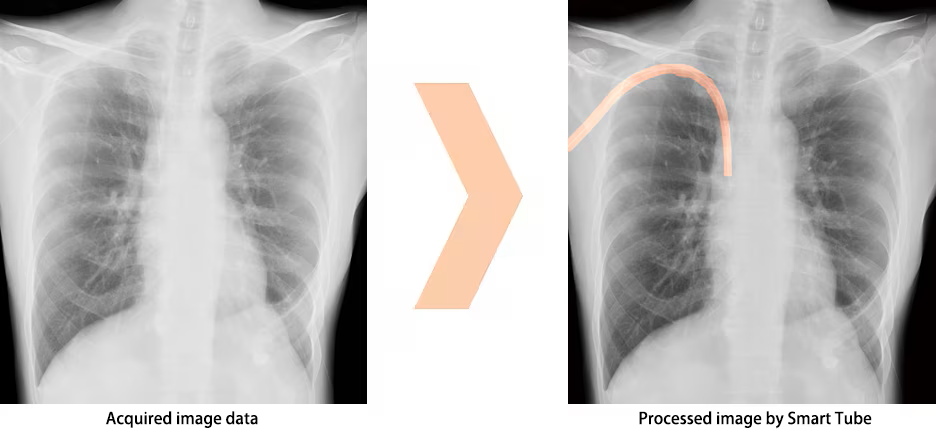

Smart Tube : Tube and catheter verification support software OPTION

Developed with AI technology, Smart Tube enhances potential areas of tubes and catheters from images, supporting position verification. *1)

Display images processed by Smart Tube on the main monitor. *2)

Processed image by Smart Tube

- *1) Do not rely solely on the imaging processing capabilities of Smart Tube when verifying tubes or catheters. Use visual confirmation of images or other methods in reaching a final judgement.

- *2) The AI (artificial intelligence) technology used in Smart Tube is not a self-guided interactive learning-type AI.